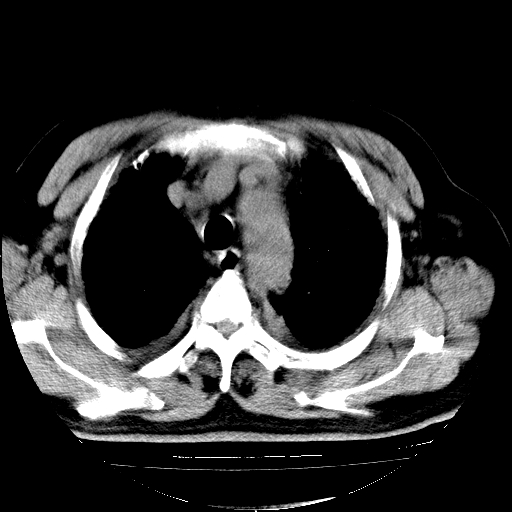

男,68岁,咳嗽、胸闷、发烧三天,查体:双肺散在湿罗音。

首先考虑特发型肺间质纤维化;两侧少量胸腔积液。

依据:1、两肺广泛条索状、网格状、蜂窝状改变。

5.双侧胸腔少量积液;双侧胸膜增厚。

双肺多发条索状、网格状及小灶状密度增高影。考虑慢支合并感染.间质纤维化,双侧少量胸腔积液

两肺广泛条索状、网格状、蜂窝状改变。肺间质纤维化,肺心病,双侧胸腔积液